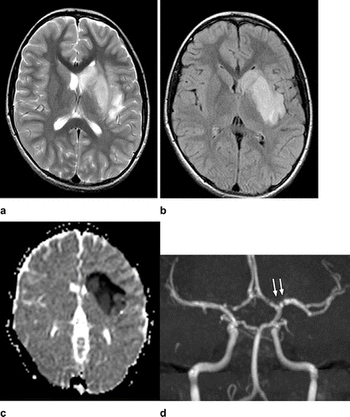

Iranian researchers diagnosed ischemic stroke in COVID-19-positive child with no other symptoms.